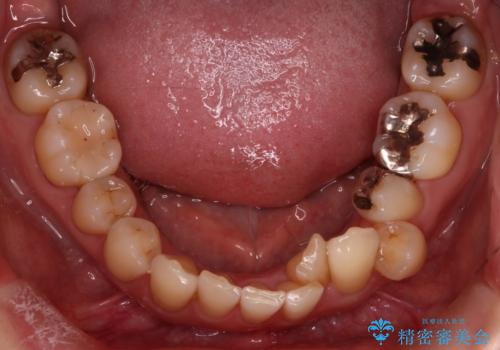

- 上下の歯の凸凹を主訴に来院されました。

他院では抜歯+ワイヤー矯正の提案をされているとのことでした。

当院での検査にて非抜歯+インビザライン矯正を提案させていただき治療を行なっております。